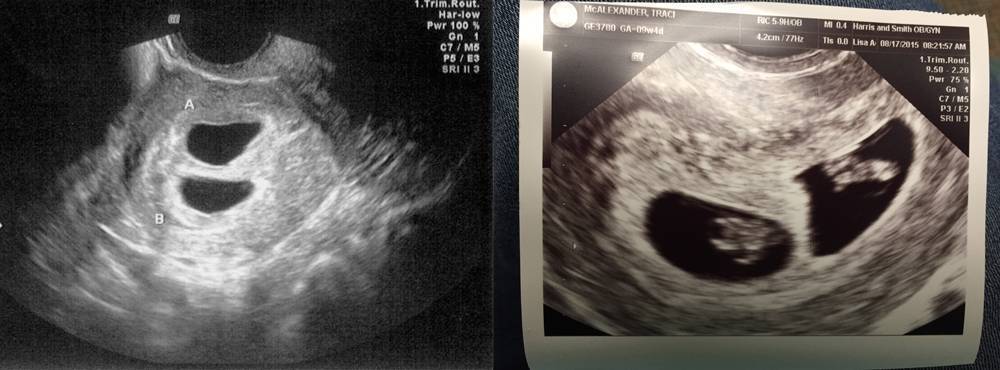

Развитие эмбриона на 8 неделе беременности